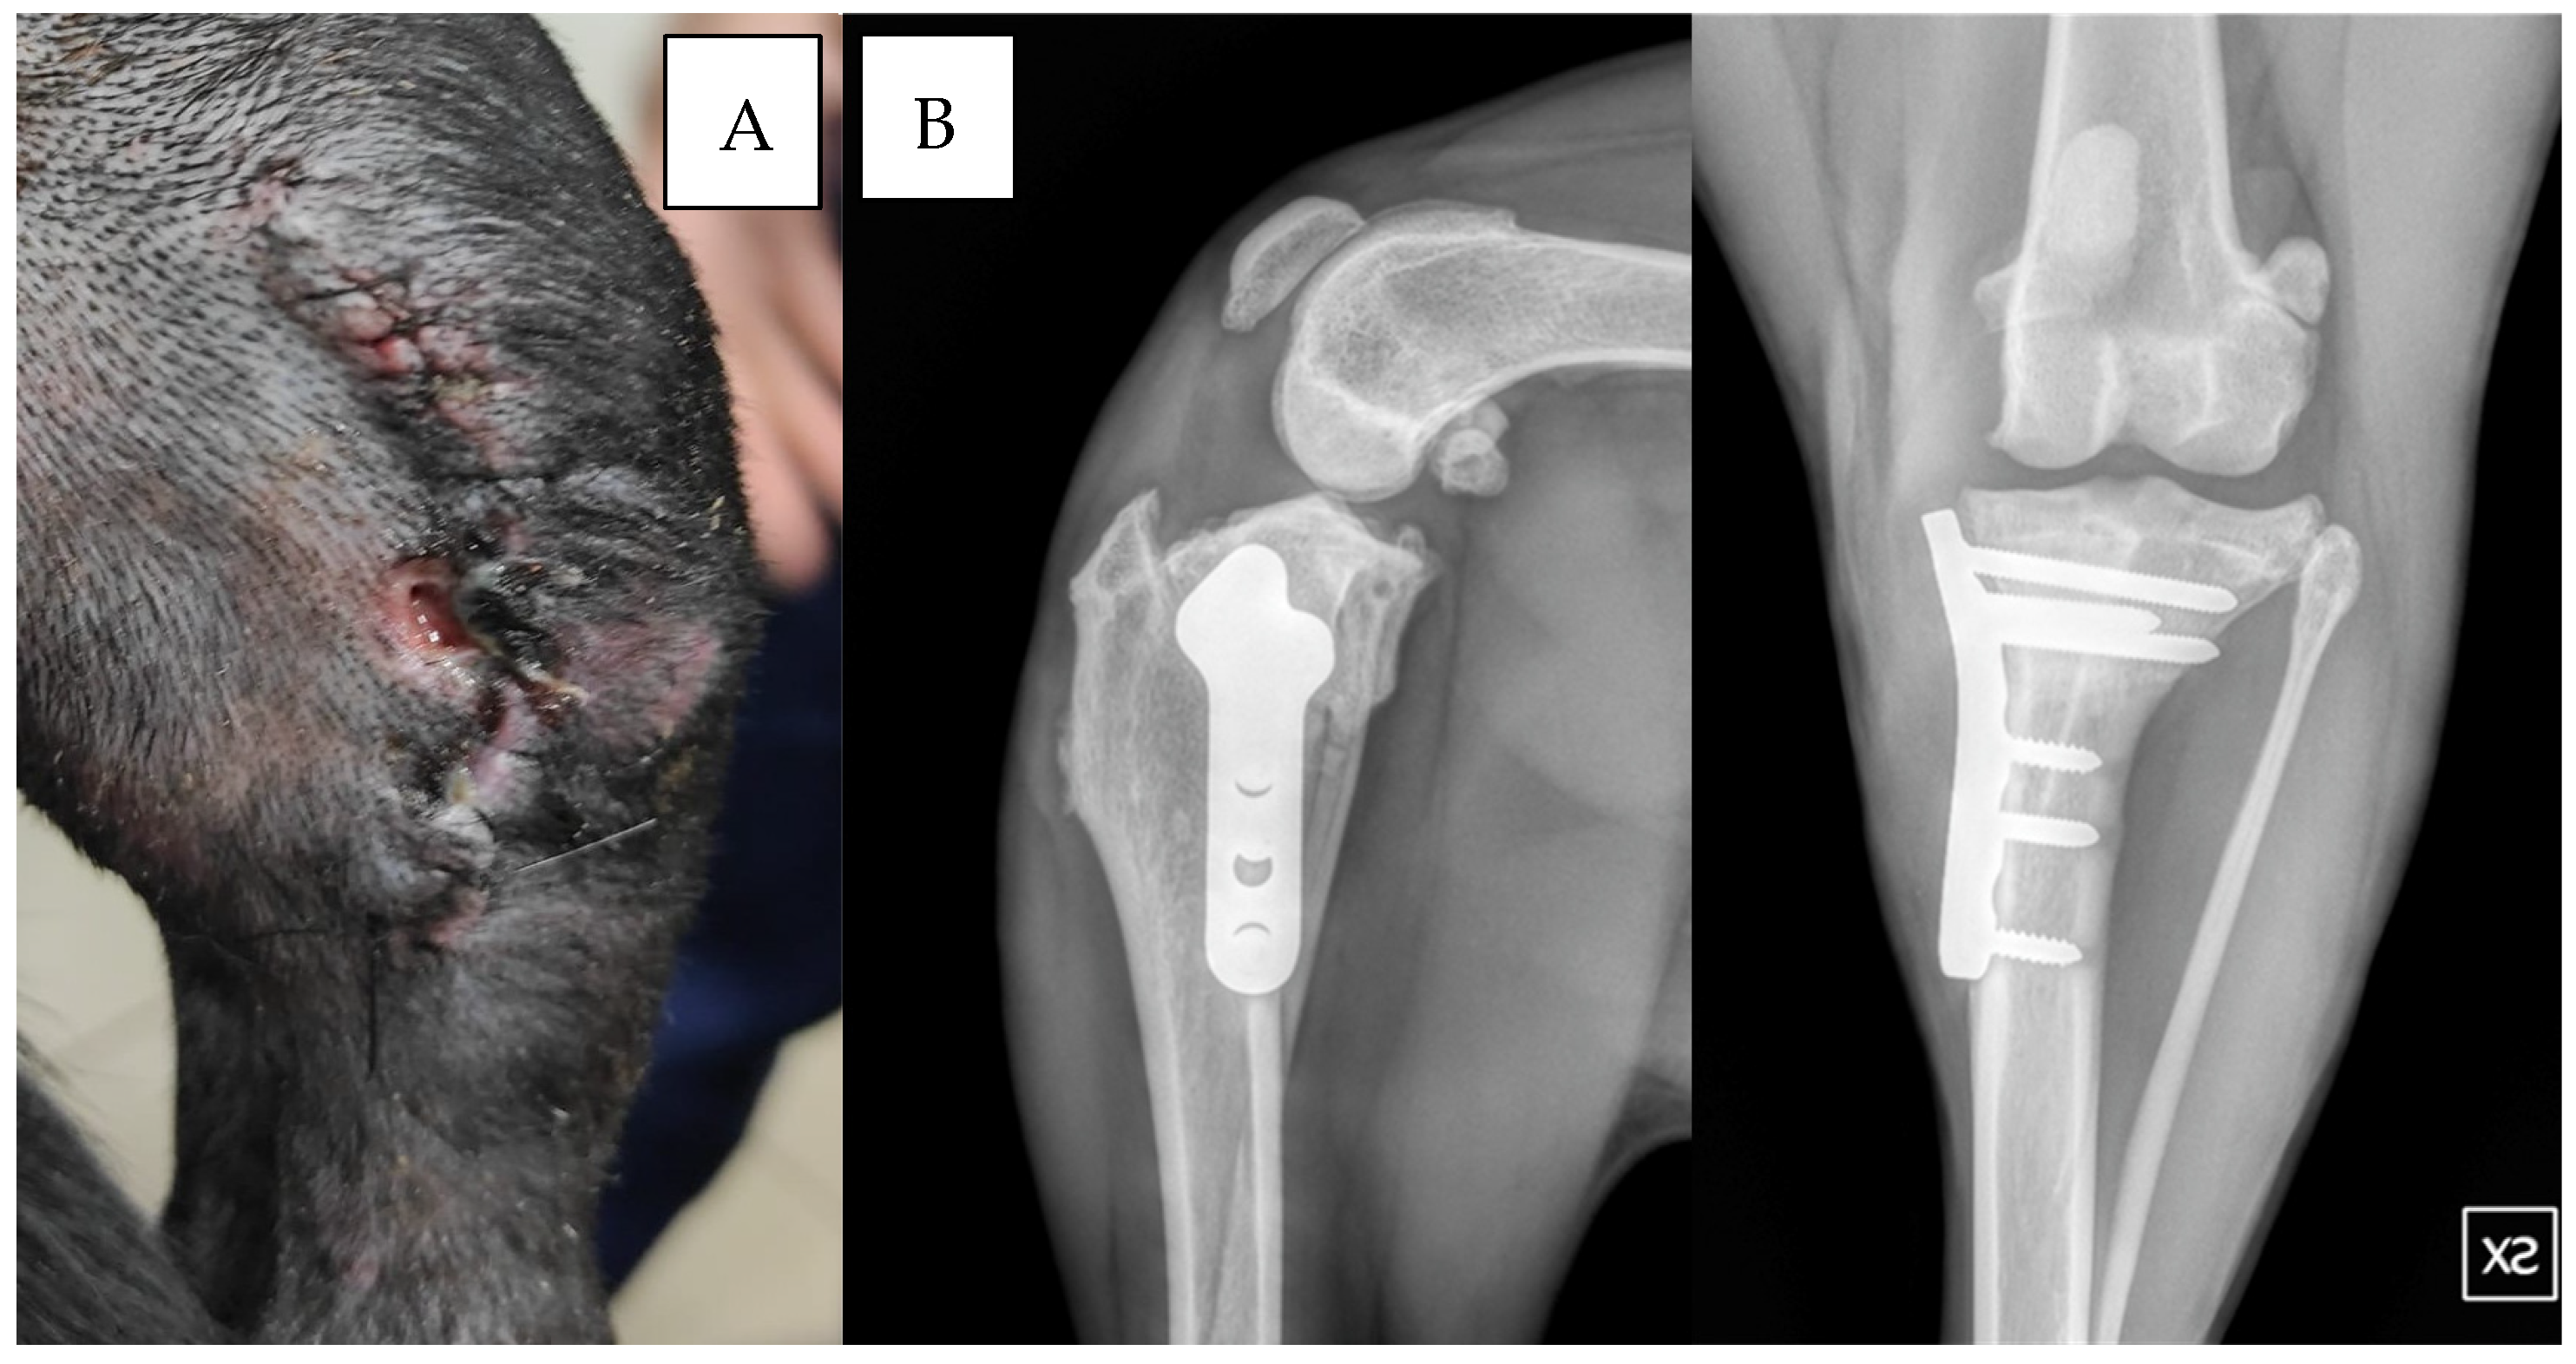

In group B, one dog exhibited wound dehiscence 10 days post-surgery (Figure 2). Staphylococcus hominis was cultured from the wound, and sensitivity testing showed positive results for enrofloxacin but resistance to cefazolin, and amoxicillin/clavulanic acid was present.

In another dog from group B, wound discharge was noted 15 days post-surgery. In a third case from group B, the culture revealed Serratia marcescens (Figure 3A). The antibiogram showed sensitivity to enrofloxacin and marbofloxacin, while resistance to cefazolin and amoxicillin/clavulanic acid was observed.

Dogs with wound dehiscence underwent surgical wound cleansing and received 20 days of oral antibiotics (enrofloxacin 5 mg/kg BID). Radiographs revealed ossification 90 to 100 days post-surgery (Figure 3B).

Figure 2. Dog: Pitt bull, f, 5 years old, left TPLO. Wound dehiscence was observed 10 days after surgery. Staphylococcus hominis ssp. was isolated from the culture swab (A). The two radiographic projections show the control 90 days after surgery, note the absence of any signs of SSI (B).